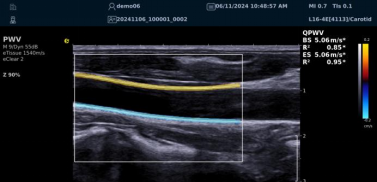

(五)QPWV 彩色脉搏波传导速度定量技术

QPWV 技术是3377体育医疗的极速脉搏波速度测量技术,对脑卒中诊疗优势明显:

? 可进行动脉壁运动速度 - 时间彩色成像,直接测量单点脉搏波传导速度及相关参数(如 BS、ES 时的速度及标准差)。

? 能在血管内中膜增厚前的内皮功能不全阶段检测异常,对早期动脉硬化评估极具临床价值。

? 操作简单直接,无需附加设备,影响因素少,检测快速、重复性和稳定性高。